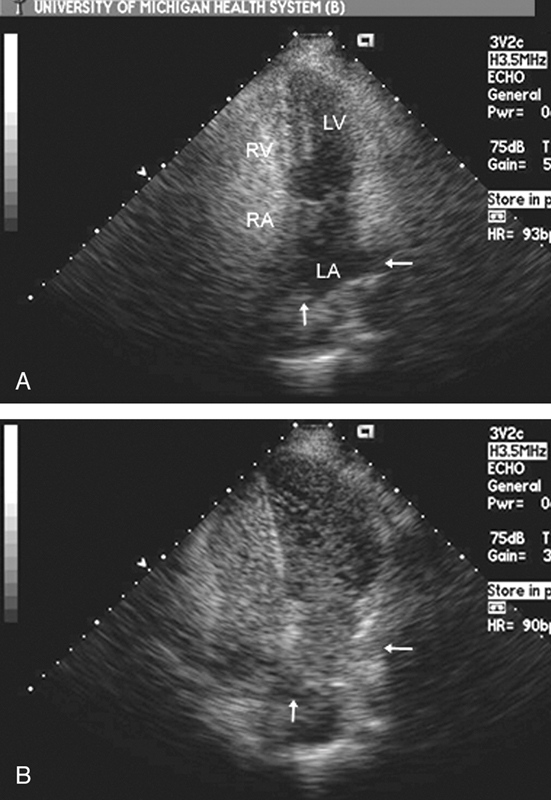

فحوصات تشخيصية لبعض امراض القلب والشرايين التاجية